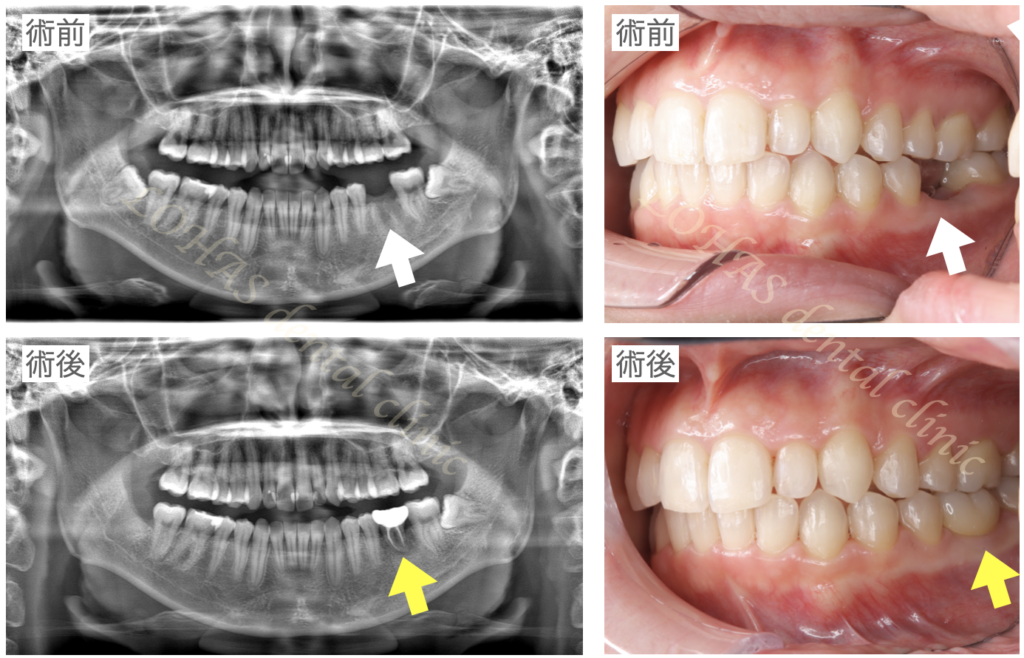

実際に当院で親知らずの移植を行った患者様になります。

この患者様は年齢的にも30代前半とお若く、できればインプラントのタイミングを遅らせることができればと考えました。

この方の場合は下の親知らずが埋まっていたのですが、周りの歯根膜を傷つけることなく抜歯ができるだろうと判断したため、下顎の親知らずを移植に用いました。

決して簡単な症例ではなかったですが、とても良い結果を得ることができました。

術後3年程度経過していますが、問題なく過ごしていただいています。

こちらの症例について詳しくはこちら:歯が折れて抜歯になった部位に、埋まっている親知らずを自家歯牙移植することでインプラント治療を免れることができた症例